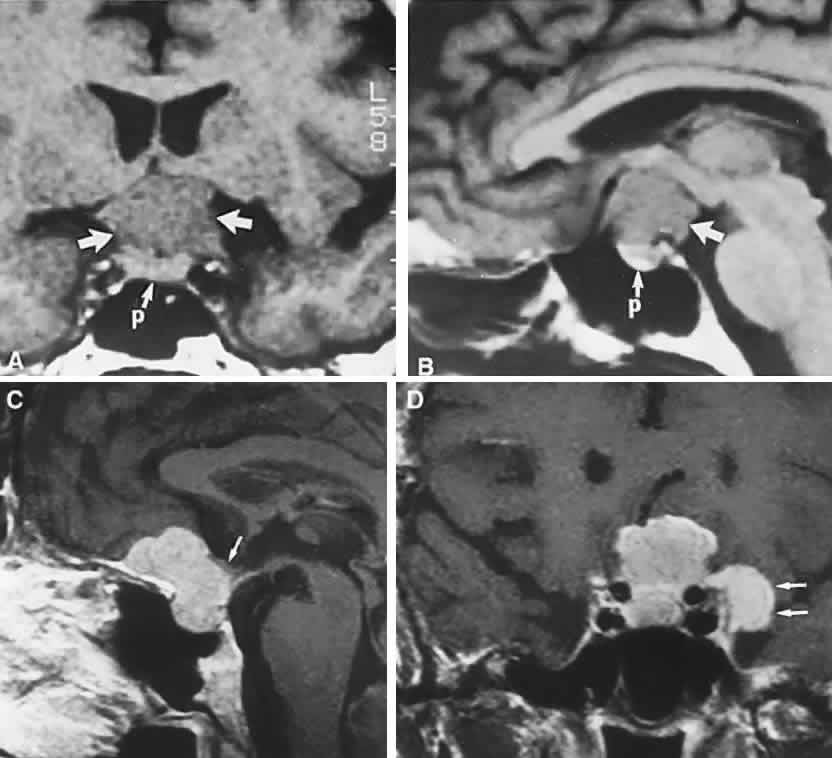

In previous decades, chiasmal interference with optic atrophy, but “normal” plain skull films, was referred to as “Cushing's syndrome of the chiasm,” caused by meningiomas, aneurysms, or other noncalcified suprasellar lesions. The modern neuroimaging techniques of enhanced CT, “bone-window” protocols, and gadolinium-contrasted MRI are now exceedingly sensitive in disclosing meningiomas or other parachiasmal masses (Fig. 4). At present, contrast-enhanced CT or MRI precisely demonstrate extra-axial tumor configuration; CT is superior in disclosing calcification or bone changes, but it is inferior for assessing suprasellar or intrasellar extension, postsurgical changes, and vascular displacement or encasement.76 Whether MRI or even MR angiography obviates standard selective arteriography, especially when surgical intervention is contemplated, is moot.

Fig. 4. Magnetic resonance imaging of a suprasellar meningioma (TR, 600 milliseconds; TE, 20 milliseconds). A. Coronal section of a large meningioma (large arrows), isodense to brain. B. Sagittal section. Note the normal sella and pituitary gland (p). Sagittal (C) and coronal (D) sections of a planum meningioma, extending into the sella. Note the upward deflection of the chiasm (arrow in C) and extension to the cavernous sinus (arrows in D).